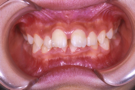

治療前

治療後

小臼歯は抜歯せずに、知歯を抜歯して治療しました。

①主訴 前歯の前突 ②診断名 上顎前突 ③年齢 16歳 ④使用装置 エッジワイズ装置 ⑤抜歯部位 下あご左右知歯 ⑥治療期間 約2年 ⑦治療費概算 90万円